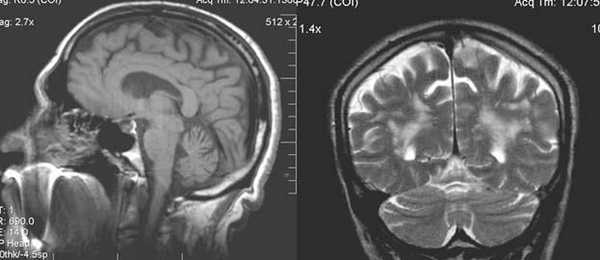

Сочетание мультифокальных очаговых изменений с диффузной кортикальной церебральной атрофией.

- Церебральная МРТ. На начальных стадиях МР томография мозга не визуализирует патологические изменения. В период клинического разгара выявляется атрофия, наиболее выраженная в фронто-париетальной коре, таламусе, хвостатом ядре, скорлупе.